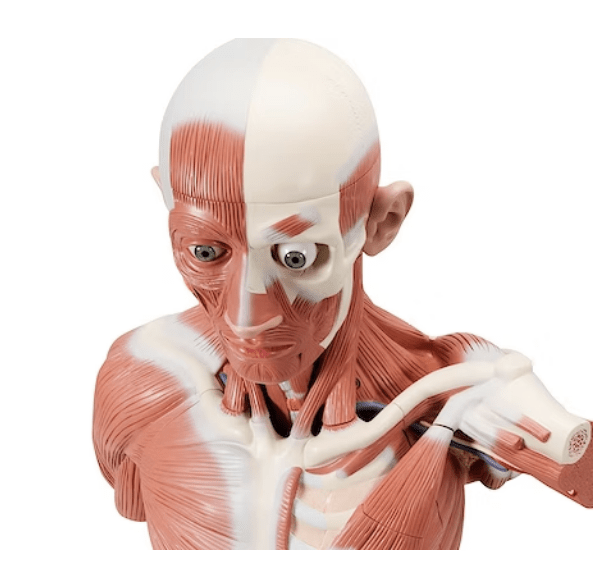

Denna skallmodell erbjuder den mest verklighetstrogna benstrukturen, den mest exakta återgivningen av de anatomiska detaljerna och känslan av att röra vid äkta ben. Dessutom är benfärgen något gulaktig, vilket gör att skallmodellen framstår som mer realistisk. Den är tillverkad i SOMSO-plast av tillverkaren SOMSO, som är världskänd för mycket hög kvalitet. Modellen används bland annat inom läkarutbildningen i Danmark.

Modellen är gjuten i en storlek som motsvarar en vuxen person. Längden är 17,5 cm och bredden 14,1 cm. Den väger cirka 800 gram. Skalkepsen ("toppen") kan tas av, så bl.a. skallbasen (basis cranii interna) kan studeras. Skalkepsen hålls på plats via praktiska metallkrokar och små plastnålar (plaststiften syns bara när locket tas bort). Hela vägen runt skallen framstår monteringen jämn och diskret när kaloten är påsatt (se bilderna till vänster).

Mandibeln är fäst med en fjäder. Den kan enkelt och snabbt demonteras. Skallemodellen kan alltså delas upp i 3 delar.